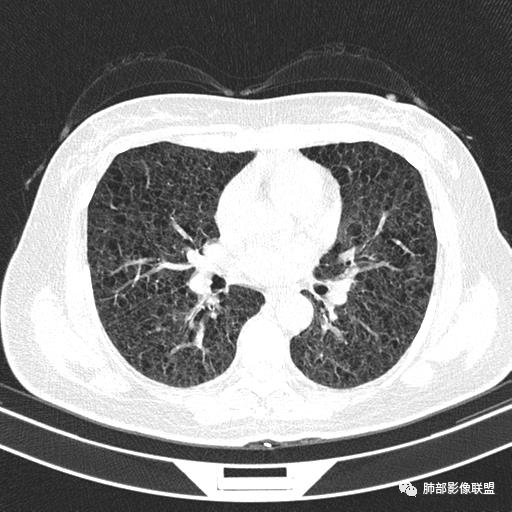

双肺弥漫囊腔,累及肋膈角,囊腔形态相对规则单一。

CT平扫示双肺弥漫分布大小不等囊状薄壁透光区,无内、中、外带分布差异,间质稍示增厚。拟LAM

中年女性育龄期妇女,咳嗽气喘,无吸烟史,有苯吸入史。影像:双肺弥漫均匀小囊腔,无明显分布优势,囊腔形态欠规则,壁薄,部分囊腔边缘血管征,伴双肺弥漫磨玻璃影,无结节,考虑lam,鉴别苯中毒肺损伤,囊腔多有分布优势,小叶中心分布为主,形态规整等

CT表现:双肺弥漫大小不等的薄壁囊腔,囊壁<2mm,外形规则,血管影多位于囊腔周围,囊腔之间肺组织正常,随着疾病进展到晚期,囊腔变大、增多,不可胜数,囊腔可融合成较大的囊,与肺气肿相似,形成间质性肺纤维化。部分病例可出现结节影。